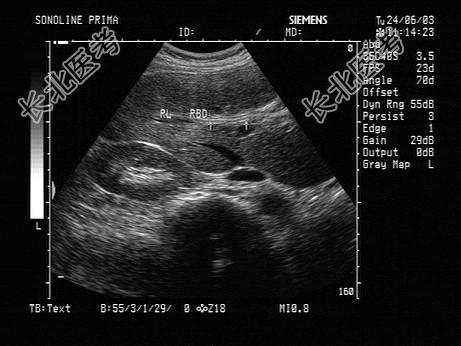

- 单项选择题女性患者,34岁, 经常反复发作剧烈的右上腹痛,加重1天。声像图如图所示, 最可能的诊断为   (   )

A、肝内胆管积气

B、引流管回声

C、肝内胆管结石

D、肝内胆管蛔虫

E、肝内胆管癌